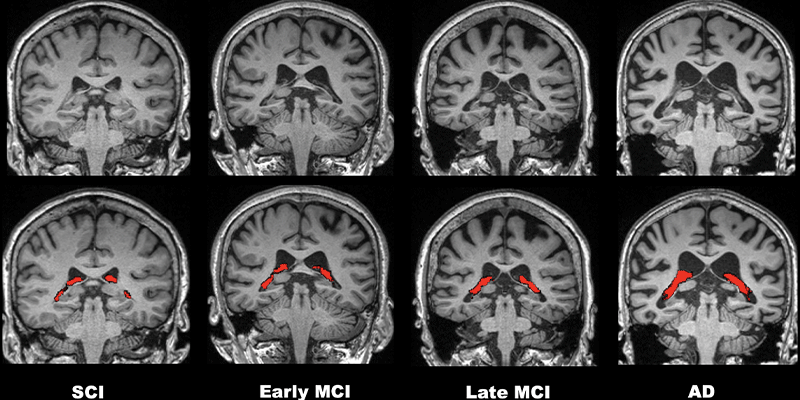

Comparisons of four representative 3.0-T brain MRI scans of choroid plexus (CP) volume (red) according to disease stage over the cognitive impairment spectrum. CP volume is greater in the patient with Alzheimer disease (AD) than in those with subjective cognitive impairment (SCI) or mild cognitive impairment (MCI). All patients were 75-year-old women.

Choi et al, Radiology 2022; 000: 1-11 © RSNA 2022